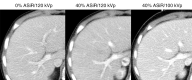

Results: With 40% ASIR implementation, the average relative dose reduction for chest CT was 39% (2.7/4.4 mGy), with a maximum reduction of 72% (5.3/18.8 mGy). The average relative dose reduction for abdominopelvic CT was 29% (4.8/6.8 mGy), with a maximum reduction of 64% (7.6/20.9 mGy). Beam current modulation was unnecessary for patients weighing 40 kg or less. The difference between 0% and 40% ASIR noise magnitude was less than 1 HU, with statistically nonsignificant increases in patient CNR at 100 kVp of 8% (15.3/14.2; P = .41) for chest CT and 13% (7.8/6.8; P = .40) for abdominopelvic CT.

Conclusion: Radiation dose reduction at pediatric CT was achieved when 40% ASIR was implemented as a dose reduction tool only; no net change to the magnitude of noise in the reconstructed image or the patient CNR occurred.